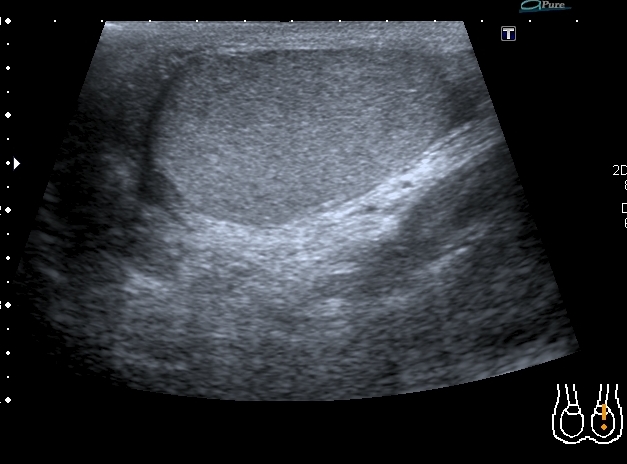

Сегодня смотрел его на контрольном УЗИ: в правой половине мошонки - небольшое количество жидкости. Яичко прежних размеров, кровоток в яичке востановился, но определяется в основном в подоболочечной зонеВ области ворот яичка - гипоэхогенный участок с нечёткими контурами. Вопрос: что делать дальше